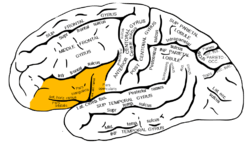

Inferior frontal gyrus(red).

Inferior frontal gyrus(red). Lateral surface of left cerebral hemisphere, viewed from above.

The inferior frontal gyrus can be subdivided into the following macroanatomical structures, shown in yellow in the top image, just below the label gyrus frontalis inferior:

- Pars opercularis (cortex posterior to the ascending ramus of the lateral fissure)

- Pars triangularis (cortex between the ascending ramus and the horizontal ramus of the lateral fissure)

- Pars orbitalis (cortex inferior and anterior to the horizontal ramus of the lateral fissure)